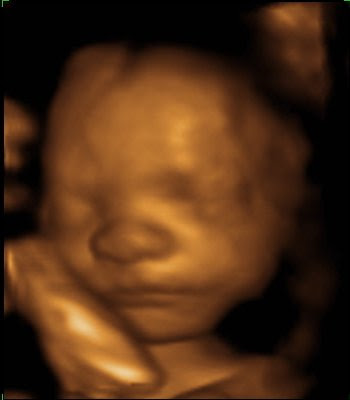

28 Weeks.

Today I got to see LB! He’s beautiful (to me) and I’m smitten even more. He seems to have an abundance of personality.

He smiles. (He frowns too.)

He’s peaceful. (He’s grouchy too.)

He sucks his thumb. I hope this means he’ll take to the breast.

He looks like he’s a sweetie-pie.

He poses. (And puts up with the paparazzi.)

I’m so in love. I can’t wait to meet him face to face.

What a wonder technology is. Truly amazing.